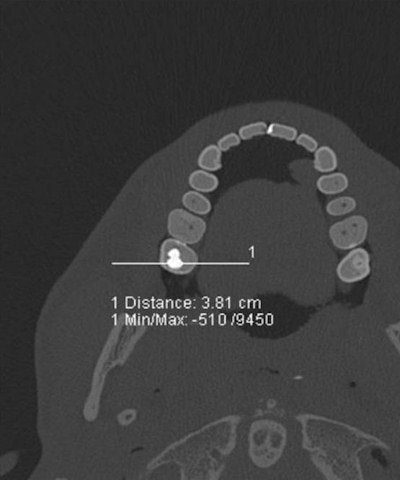

A case in point is the visualization of dental fillings. Dental x-ray plays a key role alongside DNA in identifying human remains whether in mass fatalities or single incidents when bodies have undergone alteration after death. Up to 80% of postmortem identification in the wake of the Asian tsunami in 2004 was based on dental status. Ultrahigh-resolution dual-source CT with extended CT scale has proved to reduce streak-induced artifacts and distinguish between fillings, whether composite, amalgam, ceramic, or temporary fillings, based on radiopacity in Hounsfield units, their size, and location.

Using a Siemens Healthcare Definition Flash, Jackowski has dedicated the past year of ongoing research to the development of a dual-energy application of more than 30,000 Hounsfield units and a software tool to analyze the data obtained to further characterize filling materials. This development could have implications for other areas of postmortem imaging such as bullet characterization.